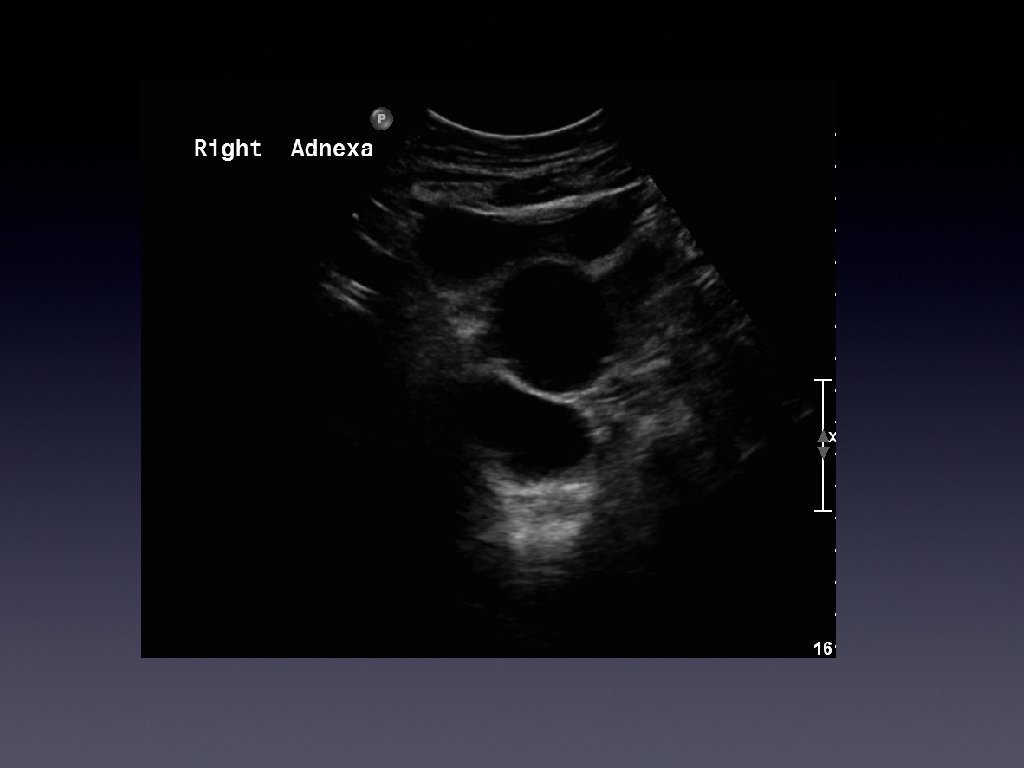

Presentation • • • 36 year old female Presented with chronic right iliac fossa

Presentation • • • 36 year old female Presented with chronic right iliac fossa pain Tenderness on palpation Bloods normal Investigated further with a pelvic ultrasound

Management • • • Patient was diagnosed with an infected hydrosalpinx She was taken

Management • • • Patient was diagnosed with an infected hydrosalpinx She was taken in for surgery Surgery revealed it was an appendiceal mucocoele

Learning points • • • Usually a cystic mass Variable internal echogenicity Devoid of

Learning points • • • Usually a cystic mass Variable internal echogenicity Devoid of septations Can have debris Not every tubular mass in the iliac fossa is ovarian in origin!!!!